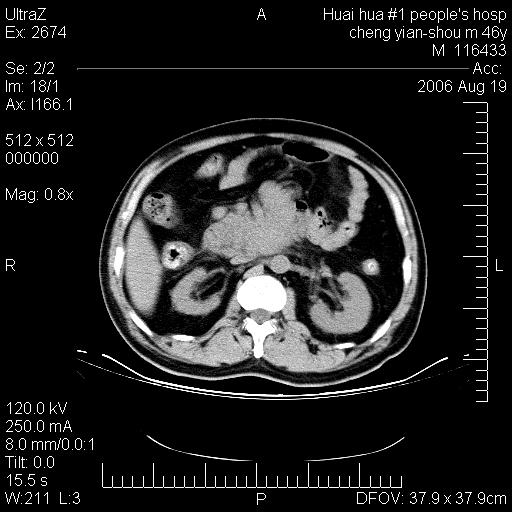

患者,男,46y。腹痛2月,消瘦。

十二指肠水平段占位,考虑间质瘤或平滑肌瘤。

肿块较大,腹膜后占位,境界欠清,周边脂肪密度较高呈条状影,有没有脂肪肉瘤可能,

缺少完整的三期图像。考虑肠系膜脂膜炎mp(肿块型)。

鉴别:间质瘤(这么大而无囊变不可思议)、平滑肌瘤/肉瘤、淋巴瘤、类癌,脂肪类肿瘤、转移瘤等。

十二指肠水平段占位,考虑间质瘤。

首先考虑小肠间质瘤。

十二指肠水平段软组织密度占位,考虑间质瘤可能性大。

腹膜后占位,境界欠清,考虑来源于十二指肠病变,间质瘤或平滑肌肉瘤可能性大。建议活检。

手术病理结果:原发性小肠恶性淋巴瘤(primary gastrointestinal lymphoma,pgil)是原发于胃肠的淋巴网织系统的恶性肿瘤,在结外淋巴瘤中居第一位,该病少见,临床无特异性,诊断困难,术前主要依靠影像学诊断。胃肠道本身具有较丰富的淋巴组织,因而胃肠原发性淋巴瘤是结外淋巴瘤最常见的部位,文献报道约占胃肠道恶性肿瘤的1%~4%,其中胃约占50%~70%,小肠约占35%~70%,结肠约占4%~6%。影像检查在pgil的诊断及分期中有重要的作用,ct是很有价值的检查方法。

胃肠淋巴瘤病理特点:胃肠道原发性淋巴瘤起源于胃肠壁固有层和黏膜下层的淋巴组织即胃肠粘膜相关淋巴组织(malt),多为粘膜相关淋巴瘤。病理上通常为非霍奇金淋巴瘤,且决大多数来源于b淋巴细胞,很少见于霍奇金淋巴瘤。胃肠原发淋巴瘤比胃肠道癌的发病率要低的多,最常见于胃,其病因可能跟幽门螺杆菌感染有关。幽门螺杆菌能引起胃粘膜损害,引起炎性及免疫反应,淋巴细胞聚集并形成滤泡,可影响胃的正常生理功能,导致胃淋巴瘤的发生。单纯性小肠淋巴瘤是常见好发于回盲末端,受累的肠段较长,可单发、多发,甚至累及整个小肠。原发性大肠淋巴瘤罕见,以直肠和盲肠最多见。病变大体观可表现为胃肠腔内外的肿块,也可表现为从黏膜下到浆膜面肠壁的纵向浸润,并且常常伴有肠系膜淋巴结肿大。任何情况下,肿瘤几乎总是导致一定程度的肠壁增厚,可对称或不对称,病变与正常组织间常无明确分界,肠腔可狭窄、正常或动脉瘤样扩张,后者主要是肿瘤在肠壁内浸润,破坏肠壁内植物神经丛所致。以上改变成为ct检测病变的病理基础。

肠道淋巴瘤的ct表现分为4类

1) 壁内浸润型, (2)多发结节型, (3)肠系膜受累伴腔外肿块型(本型就是),(4)肿块型。